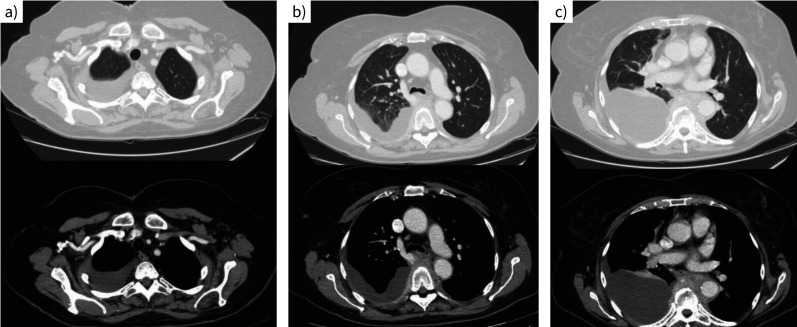

Abstract Image